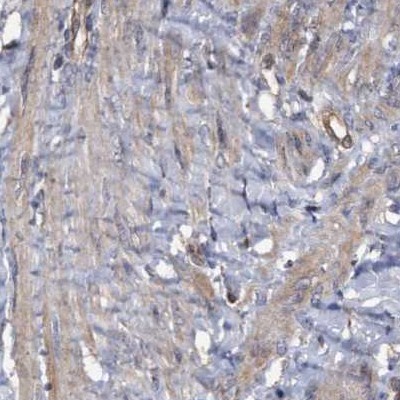

Immunohistochemistry analysis in human parathyroid gland and smooth muscle tissues using Anti-COBL antibody. Corresponding COBL RNA-seq data are presented for the same tissues.